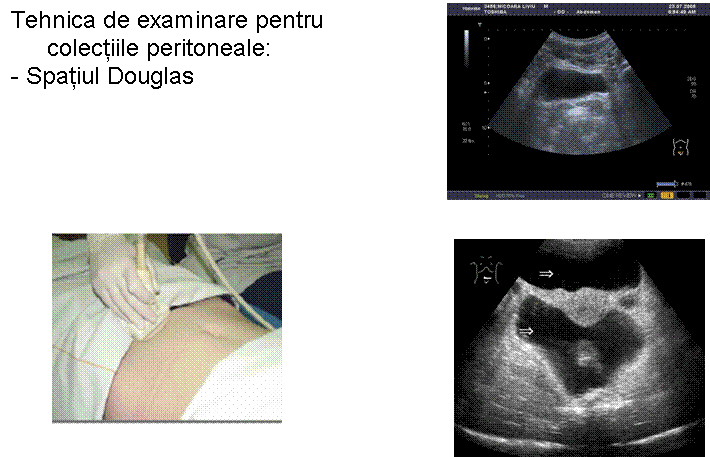

TRAUMATISM ABDOMINAL EXAMINARE FAST